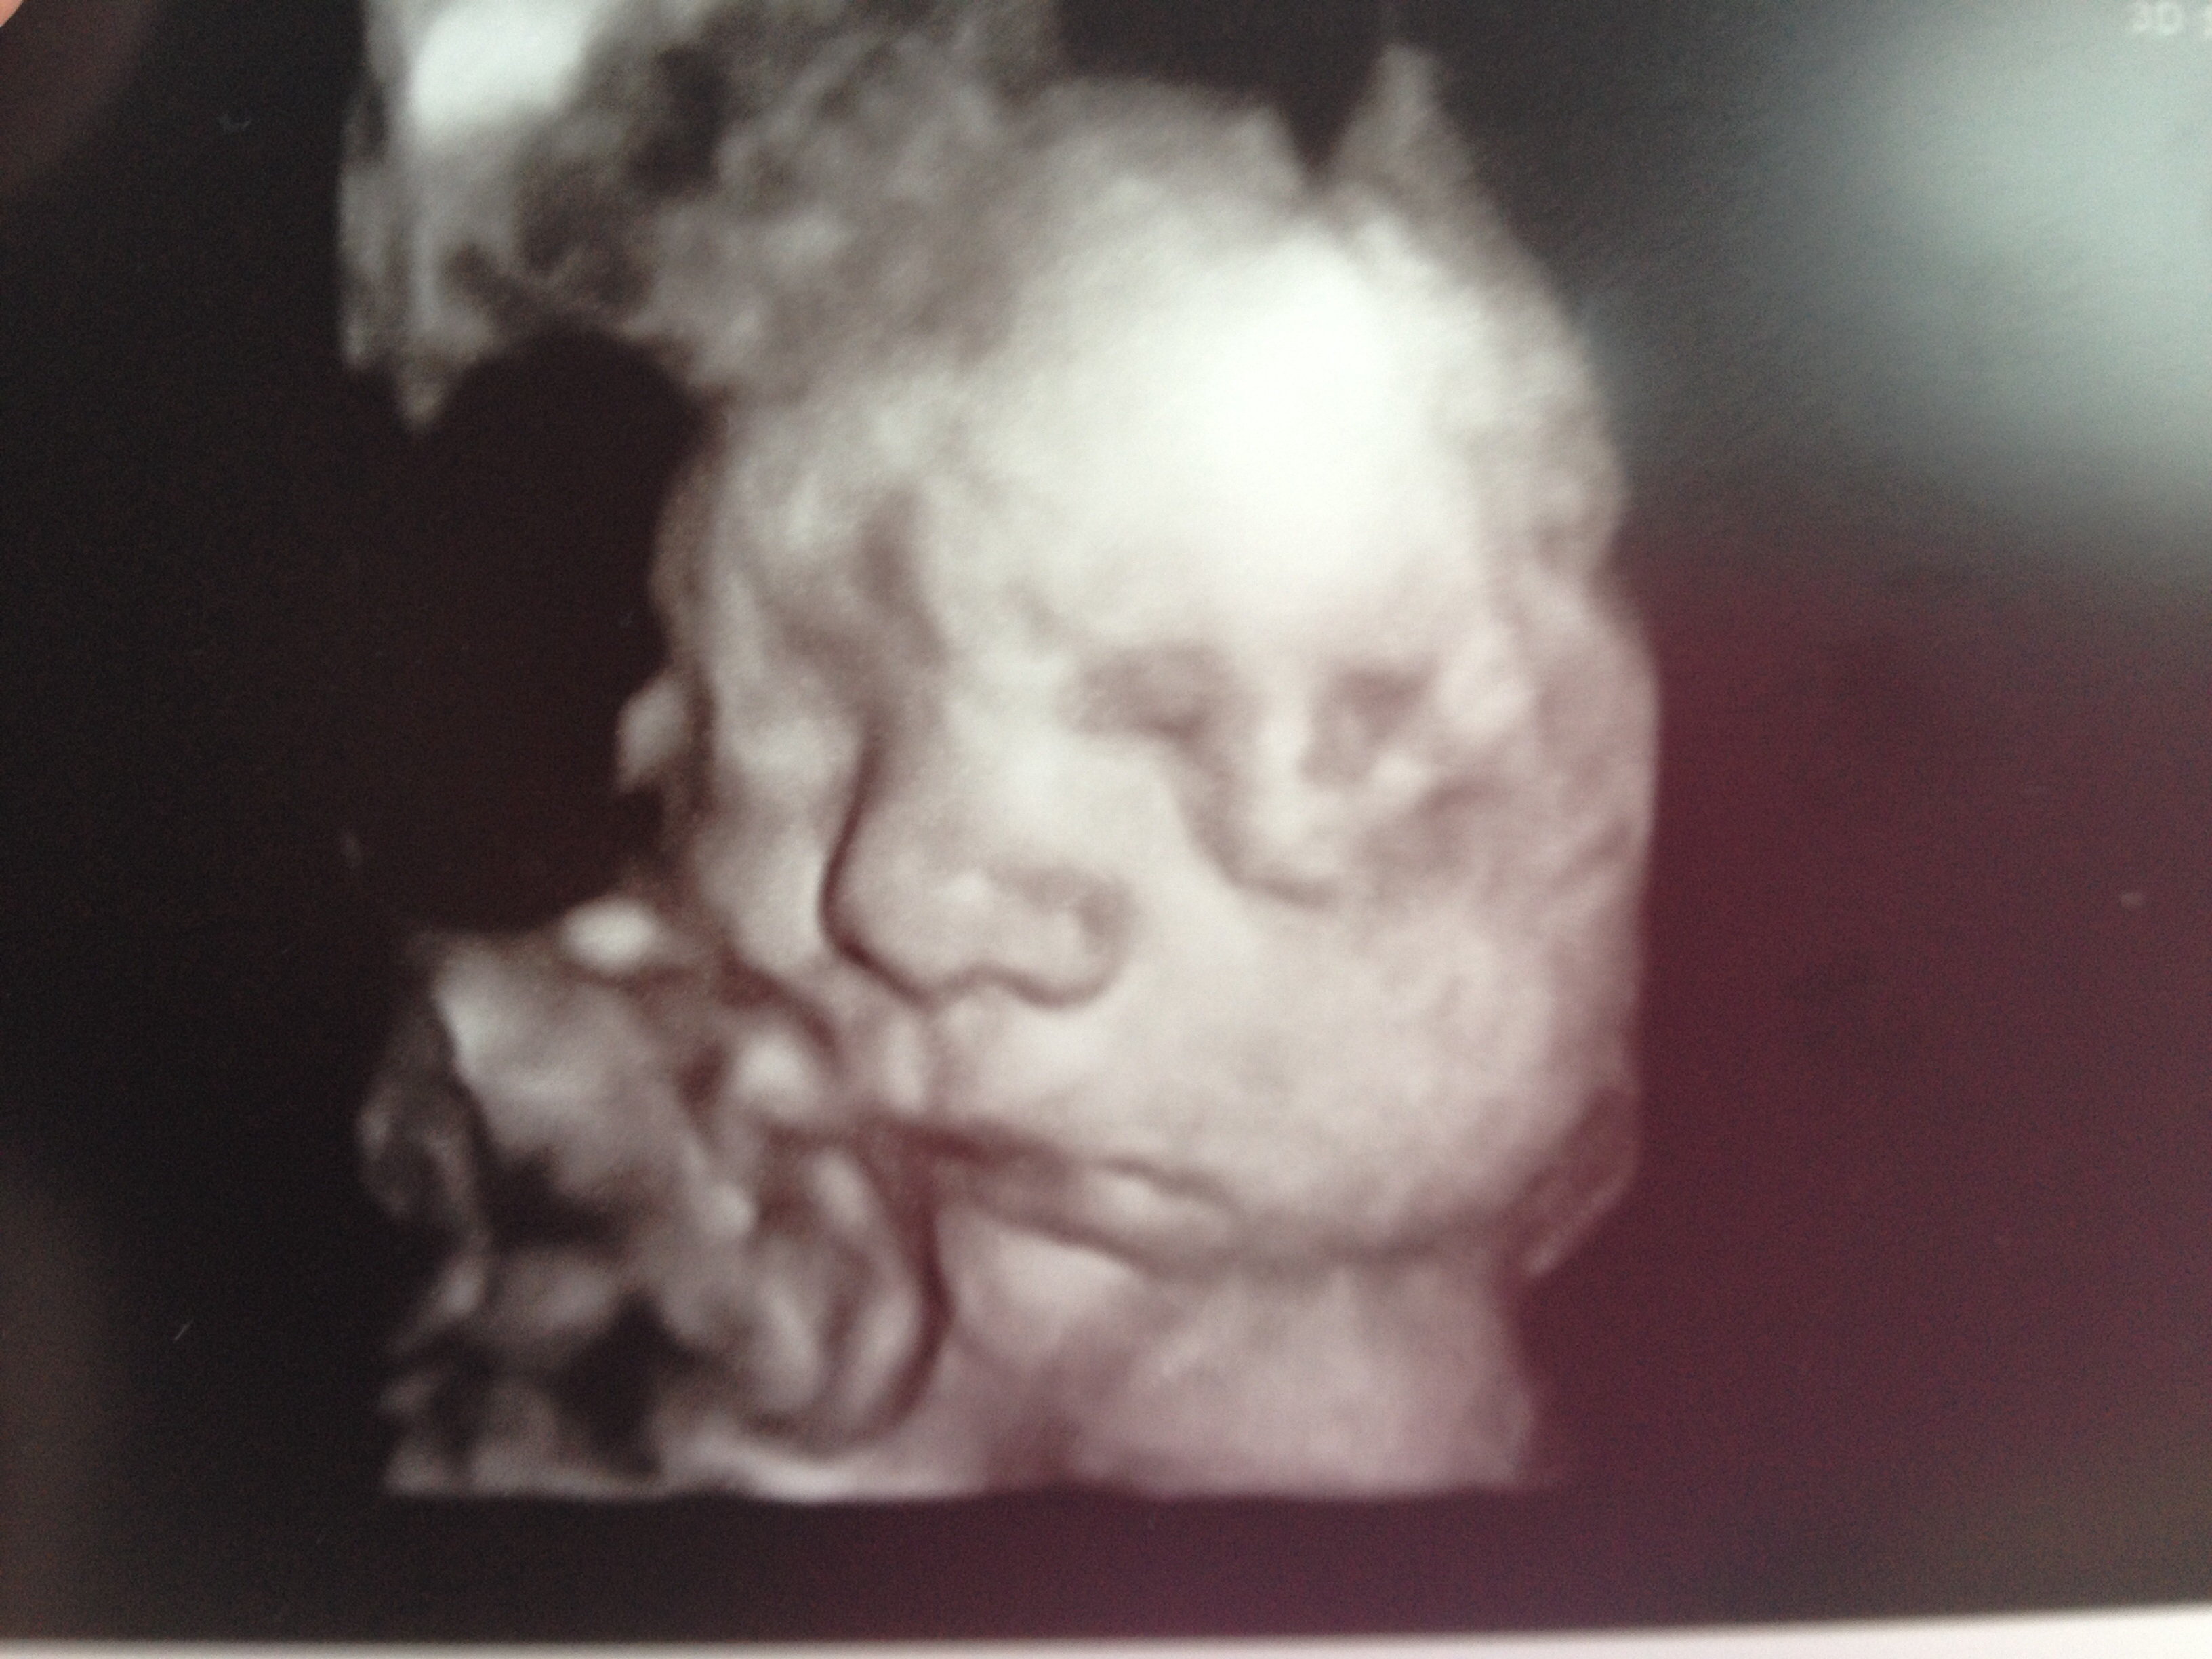

I am in love with this picture of LO. Looks just like his daddy.